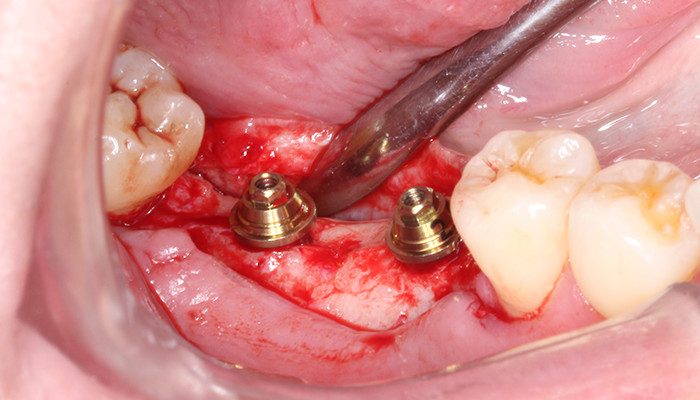

Após uma profilaxia a paciente foi submetida a anestesia local infiltrativa, retalho de espessura total e foi fresado com uma única broca com limitador de profundidade de 13 mm. Após foi conferida a posição das fresa gens com parelelizadores para posterior insta lação dos implantes. Os implantes Aikkon (3,8 × 11 mm) foram instalados 2 mm infraósseos. O torque de instalação foi de 40 N.cm (47), 60 N.cm (46) e 80 N.cm no (36). Como o torque alcançado permite a carga imediata como planejado já foram instalados os intermediários. Foi instalado o pilar Aikkon no 36 com 2,5 mm de altura de transmucoso e dois mini pilares Aikkon de altura de transmucoso 2,5 mm nos implantes 46 e 47.

8 | Implantes instalados 2 mm infraósseo.

9 | Verificação do torque de instalação do implante 36.

10 | Pilar Aikkon sendo instalado em posição.